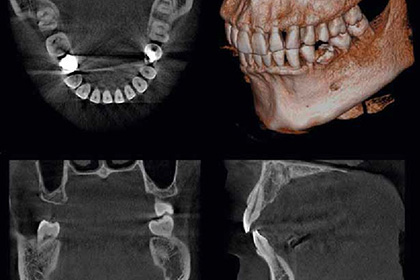

Компьютерная томография

Трехмерное изображение всех зубов, а также носовых пазух и челюстно-лицевого аппарата.

1600 рублей

Для диагностики мы используем Orthophos SL – это самый новый представитель успешного семейства 3D-рентгеновских аппаратов от Dentsply Sirona.

В стоматологических клиниках всего мира 3D-технологии становятся все более востребованными. Для более точной диагностики и объяснений пациентам процесса лечения, 3D-рентгеновская съемка предлагает ряд преимуществ. Заходящие друг на друга зубы, неожиданные пути нервных каналов, скрытые корни или аномалии ВНЧС – ценность 3D-снимков для широкого диапазона диагностики неизмерима.

Высокое разрешение (HD). При определенных показаниях, например, для визуализации тонких корневых каналов, режим высокой четкости (HD) показывает все необходимые детали.

3D-режим с низкой дозой облучения. Безопасность 3D-съемки на уровне дозы двухмерной съемки